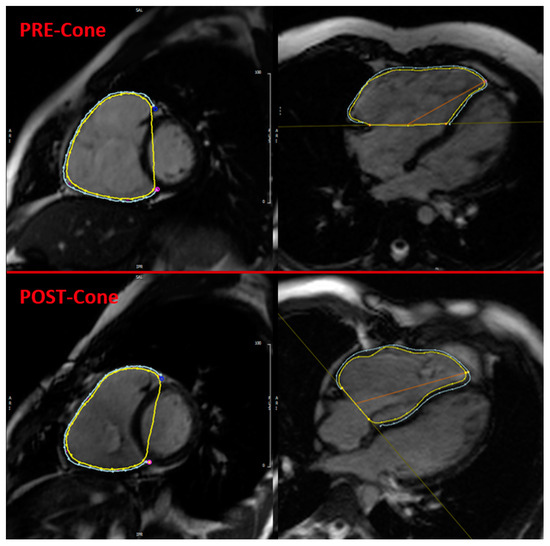

2.3. CMR Feature Tracking

2.4. Statistical Analysis